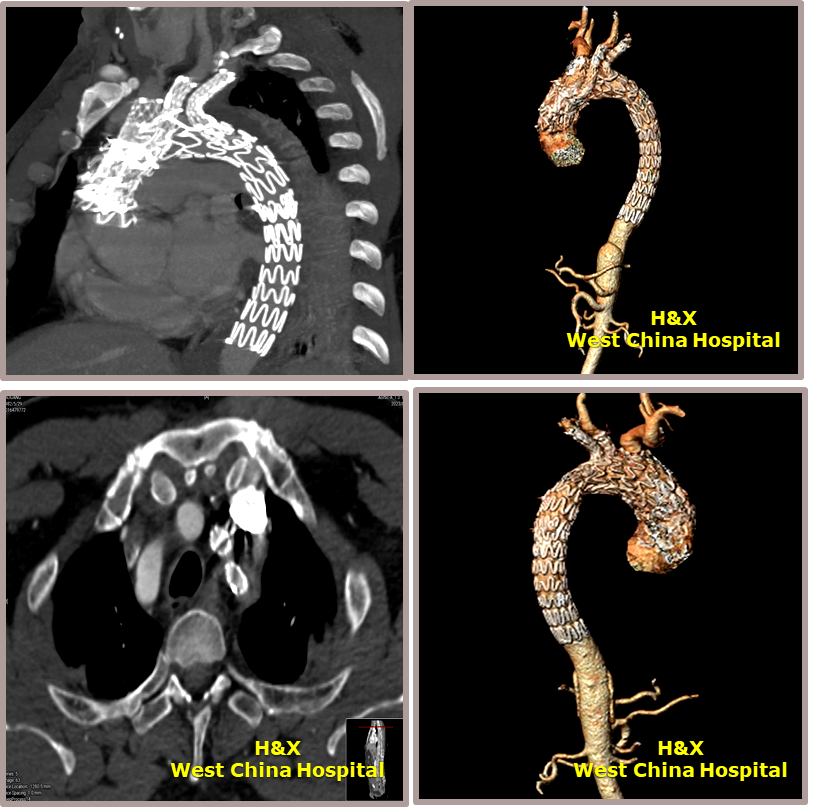

术后影像

术后CTA

术前影像

置入双分支术中支架